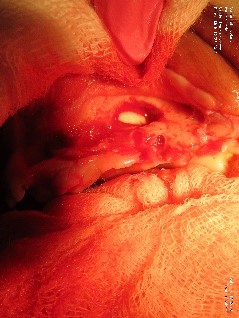

Canine stomatitis